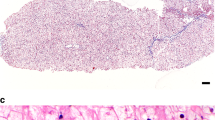

Liver histology

The presence of hepatomegaly often prompts a gastroenterologist to recommend a liver biopsy. However, if GSD VI or IX are suspected, a liver biopsy is not recommended to establish the diagnosis. In some cases, there is a role for liver biopsy, when no definitive diagnosis can be made noninvasively. There should be careful handling of the liver biopsy specimen to avoid loss of glycogen. Liver histology findings share features in common between GSD VI and GSD IX, and, there are distinguishing features such as presence of periportal fibrosis with thin septa in between lobules in GSD IX, often noted even in early stages of the disease. Liver parenchyma shows a mosaic of hepatocytes that are distended because of excessive glycogen accumulation in GSD VI and IX. Cell membranes are coarse and may have an undulated appearance. Scattered cytoplasmic vacuoles are present. Glycogen staining with periodic acid–Schiff (PAS) stain is diastase digestion–sensitive. The glycogen structure by electron microscopy shows excessive glycogen accumulation. The glycogen often has a frayed or burst appearance and is less compact than GSD I or III.23,59 Cytoplasmic lipid bodies are more likely to be present in hepatocytes in GSD IX. Children with GSD IX often show fibrosis of the portal tracts that may also be associated with inflammation.46 Liver cirrhosis may be variably present. It is more likely detected in individuals with PHKG2 pathogenic variants, but is also noted in some individuals with PHKA2 pathogenic variants.25,31,41,45,47 Fibrosis, but not cirrhosis, has also been reported in GSD VI.28